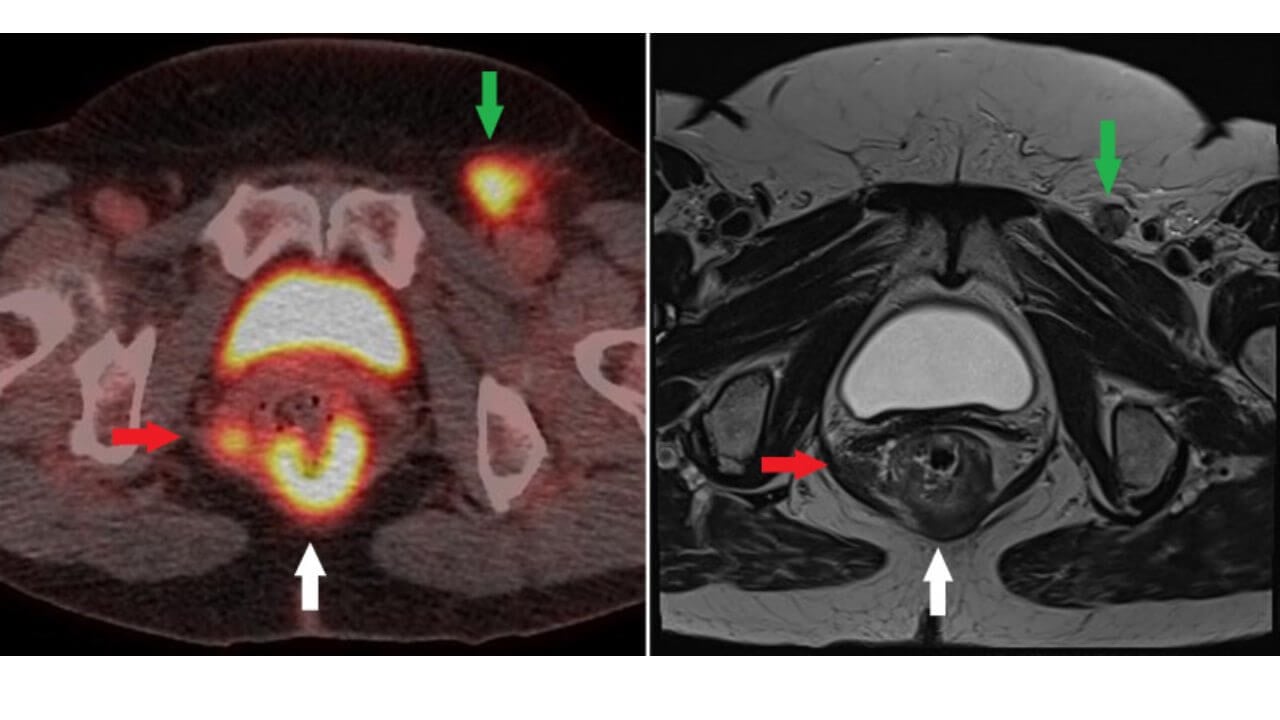

The NCCN (National comprehensive cancer network) recommends palpation of the inguinal lymph nodes with fine-needle aspiration (FNA) and/or excisional biopsy of nodes that are suspicious on clinical or radiological grounds. Evaluation of the pelvic lymph nodes by CT or MRI of the pelvis is also recommended. Fluorodeoxyglucose positron emission tomography (FDG-PET/CT) is highly sensitive in detecting involved lymph nodes. However, PET/CT is not currently part of routine staging. According to current NCCN guidelines, PET/CT is indicated for confirmation of staging in T2–4, N0, and in any T, N+ anal carcinoma [1].